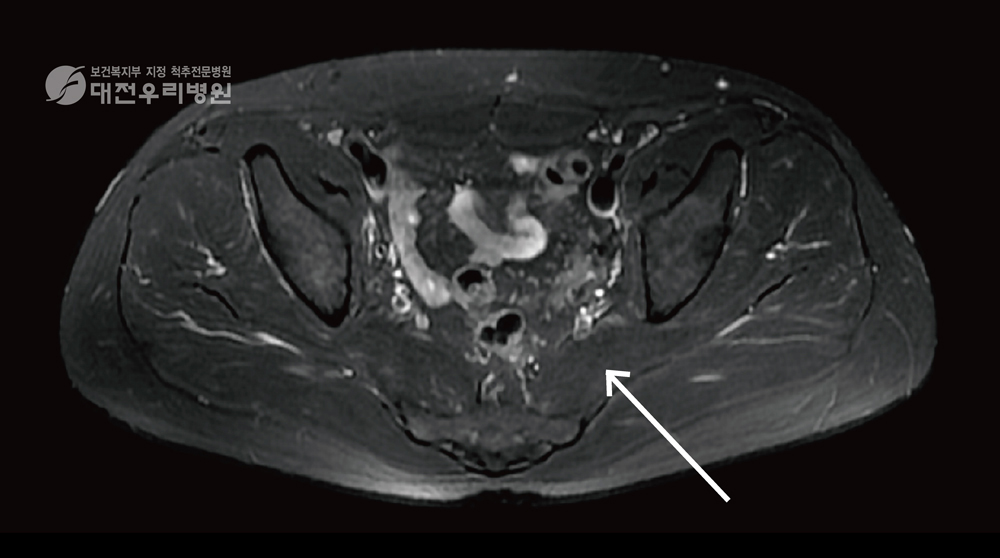

ÃÖ±Ù¿¡´Â ÀÌ»ó±Ù ÁõÈıºÀÌ ÀǽɵǸé Áø´Ü°ú Ä¡·á¸¦ µ¿½Ã¿¡ ÇÒ ¼ö ÀÖ´Â ±ÙÀ° ½Å°æ ÀڱؼúÀ» ½ÃÇàÇÕ´Ï´Ù. ±ÙÀ° ½Å°æ ÀڱؼúÀ̶õ ÅëÁõÀÇ ¿øÀÎÀÌ µÇ´Â ±ÙÀ°, ½Å°æ, °üÀý ºÎÀ§¸¦ IMS ¿ë ¹Ù´Ã·Î ÀÚ±ØÇÏ¿© Ä¡·áÇÏ´Â ÅëÁõ ½Ã¼ú·Î ¹¶Ä£ ÀÌ»ó±Ù ±ÙÀ°À» ¹Ù´Ã·Î Ç®¾îÁÖ´Â Ä¡·áÀÔ´Ï´Ù. ƯÈ÷ ÀÌ Ä¡·á´Â ¾à¹°ÀÌ ¾È µé¾î°¡±â¿¡ ºÎÀÛ¿ëÀÌ ¾ø´Â °ÍÀÌ ÃÖ´ë ÀåÁ¡ÀÔ´Ï´Ù. ±×¸®°í È¿°ú ¸é¿¡¼ ¾àÀ̳ª µµ¼ö Ä¡·á, ¹°¸®Ä¡·áº¸´Ù ÈξÀ ´õ Ź¿ùÇÕ´Ï´Ù. ƯÈ÷ ȯÀÚ¸¦ Ä¡·áÇÒ ¶§ ¾Æ·¡ ±×¸²¿¡¼ º¸µíÀÌ ÃÊÀ½ÆÄ À¯µµÇÏ¿¡ Ä¡·á¸¦ ¸¹ÀÌ Çϰí ÀÖ½À´Ï´Ù. ±×·¯¸é ÀÌ»ó±Ù Á¤È®ÇÑ ºÎÀ§¿¡ Ç÷°ü ½Å°æÀ» ÇÇÇÏ¿© ¿ÀÂ÷ ¾øÀÌ ¾ÈÀüÇÏ°Ô ½Ã¼úÇÒ ¼ö ÀÖ½À´Ï´Ù.